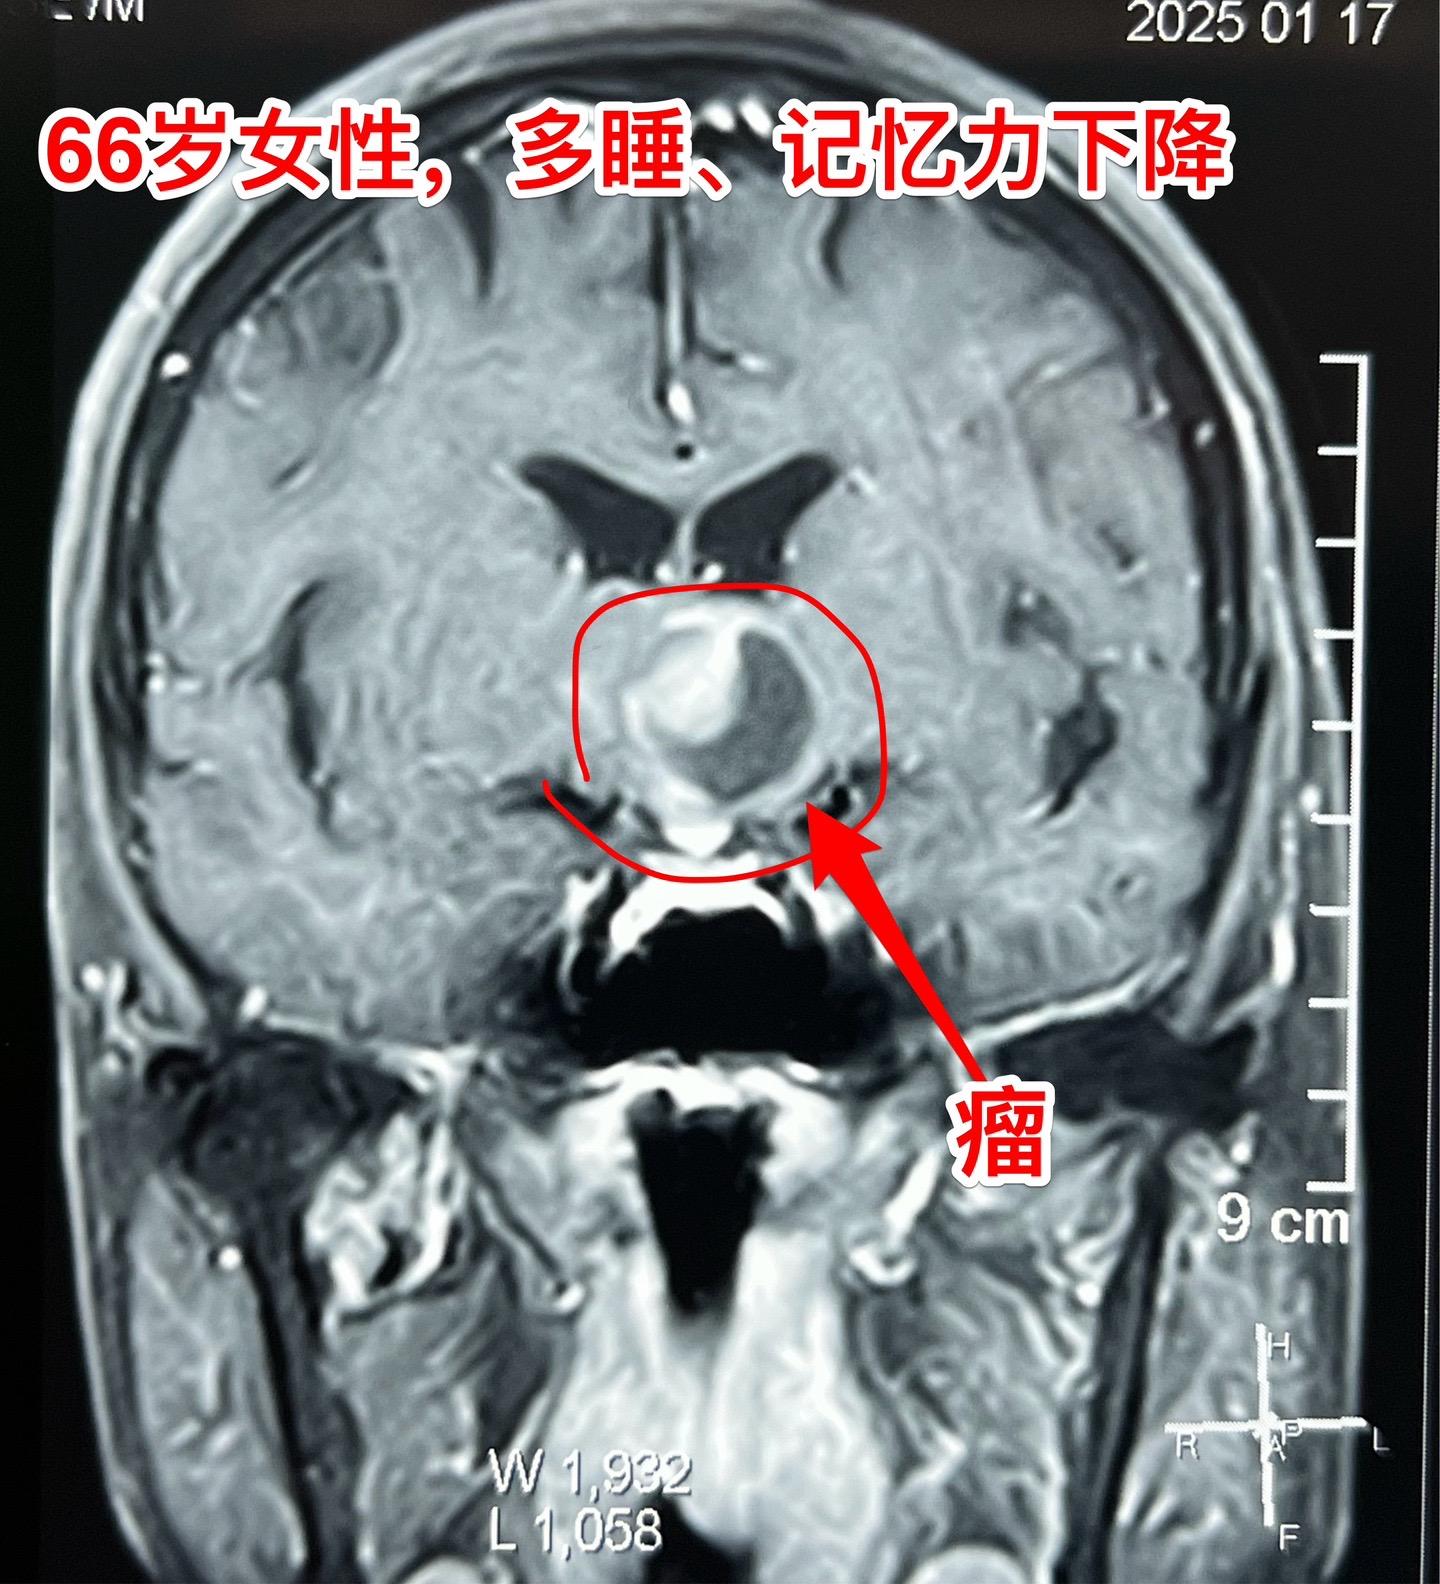

是颅咽管瘤吗?鞍区肿瘤的定性诊断是很难的。66岁女性,泰州人。因为多睡、记忆力下降在外院检查脑部发现脑部肿瘤。病人的多睡症状越来越严重。肿瘤位于鞍上区域,而且伴有脑积水。外院怀疑是颅咽管瘤?或者是别的肿瘤? 病人曾经在上海就医过,因担心手术风险,通过三博脑科医院院长找我咨询,随后决定到我院作手术。 1月24日作了开颅手术(这是我科春节前的最后一个择期手术),手术中发现肿瘤的性状不符合乳头型颅咽管瘤,分两次取标本送快速冰冻病理检查,报告考虑是胶质瘤。 下丘脑胶质